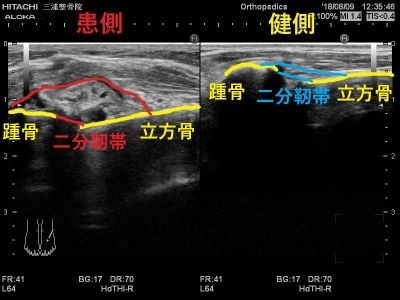

場所は外くるぶしの前方

少し足の甲側へいった辺りです。

エコーではこのように写ります。

患側では大きく腫れて

正常な靭帯線維が見えないため

二分靭帯が断裂しています。